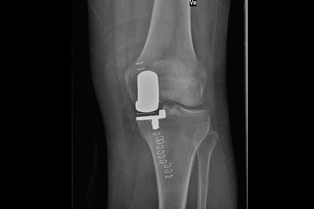

Kneprotesen er ein erstatning for øydelagde leddflater i kneet. Den består av 2 metalldelar som vert festa på lårbeinet og skinnebeinet. Leddflata på lårbeinet består av metall, leddflata på skinnebeinet av høgforedla plast. Metalldelane vert festa med eller utan beinsement. Ei totalprotese dekkjer heile leddflata både på lårbeinet og på skinnebeinet. Det pre- og postoperative forløpet er likt for alle protesetypane.